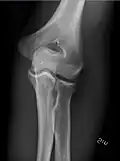

- Knee - AP and Lateral. Intra Condular projections on request

- Patella - Skyline projection

-

Right knee, anteroposterior -

Right knee, lateral -

Patella, (slightly skew) skyline